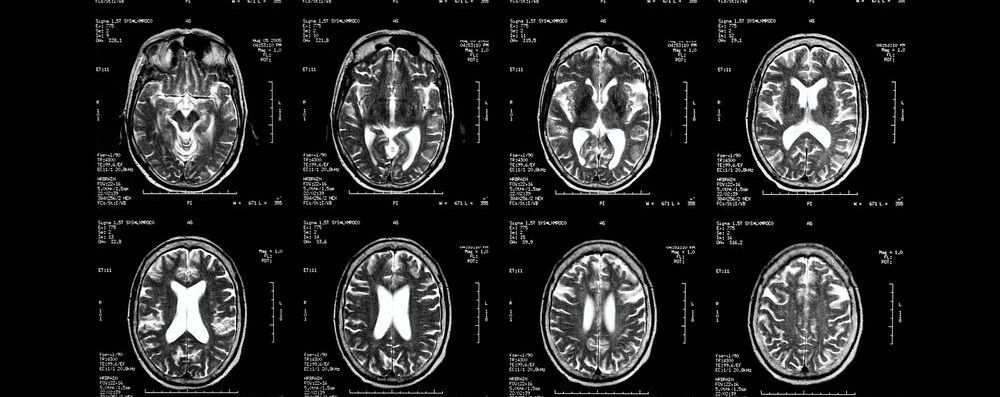

Además, a través de sus investigaciones, consistentes en el examen del cerebro de un grupo de pedófilos a través de la resonancia magnética, este científico también ha observado que hay una gran correlación entre la presencia de comportamientos pedófilos y el hecho de ser zurdo o ambidiestro.

Para comprobarlo estudiaron también por resonancia magnética los cerebros de un grupo de voluntarios, habiendo personas reconocidas como pedófilas y otras que mostraban preferencia sexual por los adultos. Se les mostraron fotos tanto de niños como de personas adultas y se comprobó cómo y cuándo se activaban las zonas relacionadas con el procesamiento de la cara y la atracción sexual, observando que las zonas activadas eran exactamente las mismas en ambos casos, pero que en los sujetos no pedófilos al visualizar las imágenes de niños se producía una inhibición de las regiones causantes de la atracción sexual que no aparecía en el otro grupo.